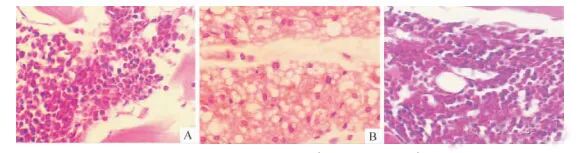

小鼠股骨病理切片显示治疗组细胞比例明显低于AA模型组,与单纯照射组结果一致。

三组小鼠大腿骨造血功能的变化(HE染色)。A: 放射治疗组B:AA模型组C:MSCs组